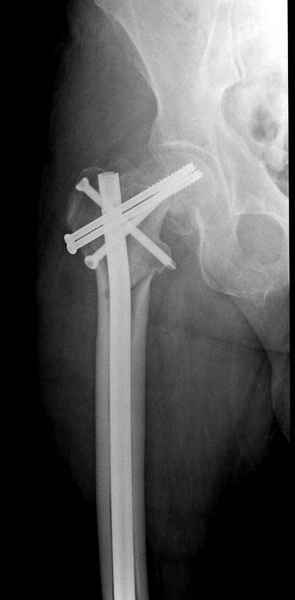

На второй день после выписки упал дома. Снимки приложены. Коллеги рекомендуют удаление шурупа и вытяжение. Что делать?

Правильно, ситуация изменилась, как говорят у нас теперь "different animal", надо решать проблему подвертельного перелома. При наличии различных вариантов фиксаторов, включая Страйкер Гамма 3, мы выбрали DePuy Antegrade Trachanteric Nail из-за многовариантности проксимальной фиксации и двойного изгиба. Вводится через вертел под 8 градусным углом, и есть достаточный передний диафизарный изгиб, предупреждающий пенетрацию дистального переднего кортекса.

Кто знает что дальше, мысленно готовы к проксимальной артропластике.

Но ведь и головка бедра сползла в варус - отчего ограничились только фиксацией подвертельного перелома, а не убрали винты и не сделали репозицию шейки?